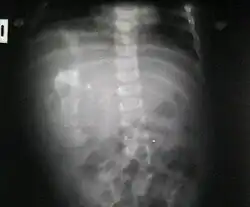

Ocurre en 1 de 1 000 000 nacimientos,[2][3] y se define como una masa fetiforme totalmente encerrada dentro del cuerpo del autósito o hermano desarrollado. Al extraerse, está envuelto en lo que parece un huevo de gallina, pero mucho más grande y extremadamente duro. El parásito, cuando es extraído y expuesto, tiene un color blanco. Una vez que se extrae, muere, ya que es un tejido totalmente dependiente de su hospedador. Al igual que en los gemelos parásitos, corazón y cerebro están ausentes o son muy rudimentarios. Puede estar más o menos organizado, con características muy variables, desde apenas una bola de tejidos hasta contener restos de pelo, hueso, manos con dedos y uñas y hasta piernas. La extirpación quirúrgica no presenta el menor problema dado que no pasan de ser tumores que pueden llegar a ser un potencial riesgo para su hospedador, debido a que se alimenta de este, representando para el hospedador una carga semiviva sin función en el organismo, y pueden llegar a malignizar.[4]